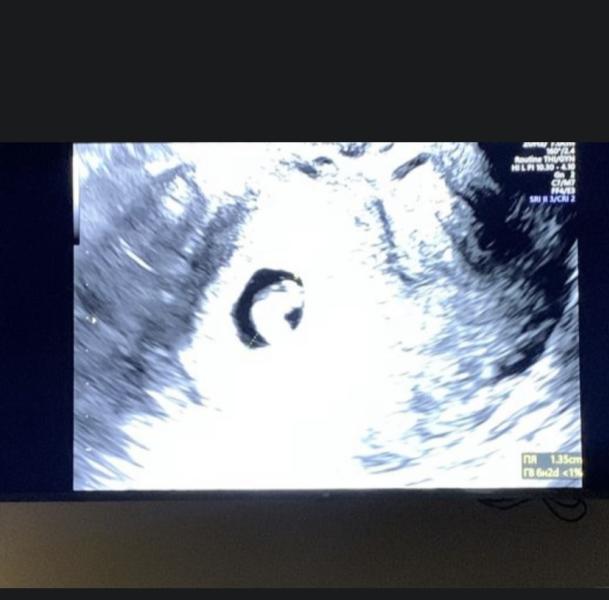

На узи увидели плодное яйцо и эмбрион, но срок не соответствовал сроку сказали подойти через 10-14 дней. Я подумала что поздняя овуляция так как цикл нерегулярный.

И вот настало время для узи, очень сильно волновалась. Посмотрела на экране малыша, услышали сердцебиение 😍 Но говорят опять срок не соответствует+ диспропорция плодного яйца и эмбриона. То есть свд меньше чем ктр плода, проще говоря плодное яйцо там на 5,3 нед а сам эмбрион на 6,5 ( точный срок не помню это примерно говорю). Узистка сказала потом сравнится, в заключении написали развивающаяся беременность , моему счастью не было предела но чувство тревожности не покидала меня.

Приехала домой и обнаружила что у меня выделения, цвет бордово-коричневый какой то..вечером опять коричневые выделения со слизью , позвонила в скорую повезли в гинекологию, назначили сохраняющую терапию и отправили домой. Каждый день мазало, сходила ещё раз на узи ( в другую клинику) , там опять диспропорция, выросли на несколько дней, а главное было сердцебиение🙏🏻 Сказала что есть гематома, поэтому и мажет. Чуть Успокоилась . Сходила к своему гинекологу, открыла больничный и я лежала дома отдыхала.

Очень сложно, смотрю на фото узи , тестов и хочется плакать 😞